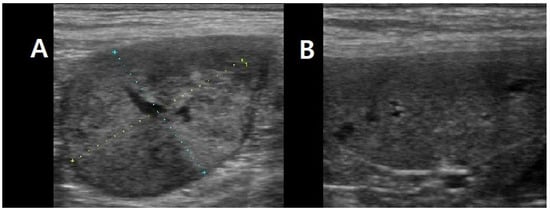

To further characterize the lesions and assess for metastatic disease, computed tomography (CT) was performed. No pulmonary metastasis was detected; however, multiple intra-abdominal masses with suspected metastatic lesions were observed. The retroperitoneal mass was delineated as a 4 × 3 × 3 cm lesion arising from the left adrenal gland, consistent with a tentative diagnosis of adrenal tumor. The spleen was enlarged and contained multiple nodular masses, while the mesenteric lymph nodes were markedly enlarged. In addition, a 7 mm lesion adherent to the wall of the hepatic portal vein (extraluminal mass) was detected and initially interpreted as a possible metastatic lesion (Figure 2).

Figure 2. CT images of abdominal tumors. (AC) Left adrenal gland mass (4 × 3 × 3 cm) shown in coronal, sagittal, and axial views, with arrows indicating the mass. (DF) Lesion adherent to the wall of the hepatic portal vein (7 mm) visualized in coronal, sagittal, and axial views, with arrows marking the site of vascular attachment. (GI) Splenic nodular masses demonstrated in coronal, sagittal, and axial views, with arrows identifying the nodular masses.